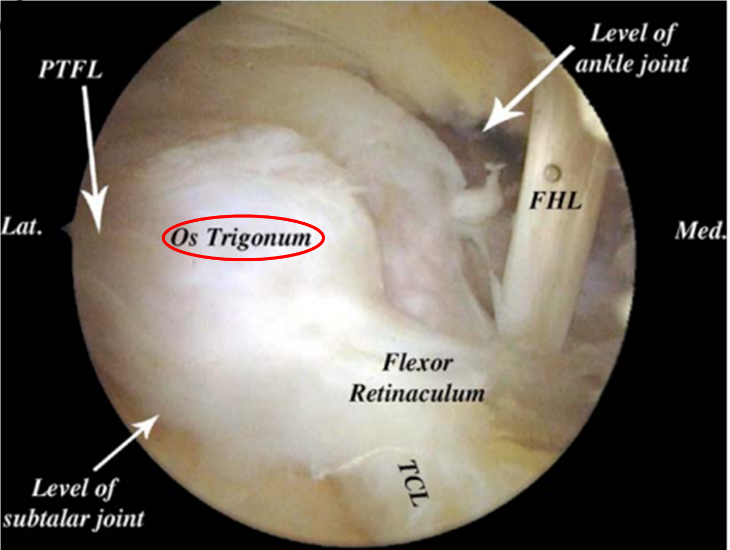

后踝关节镜手术